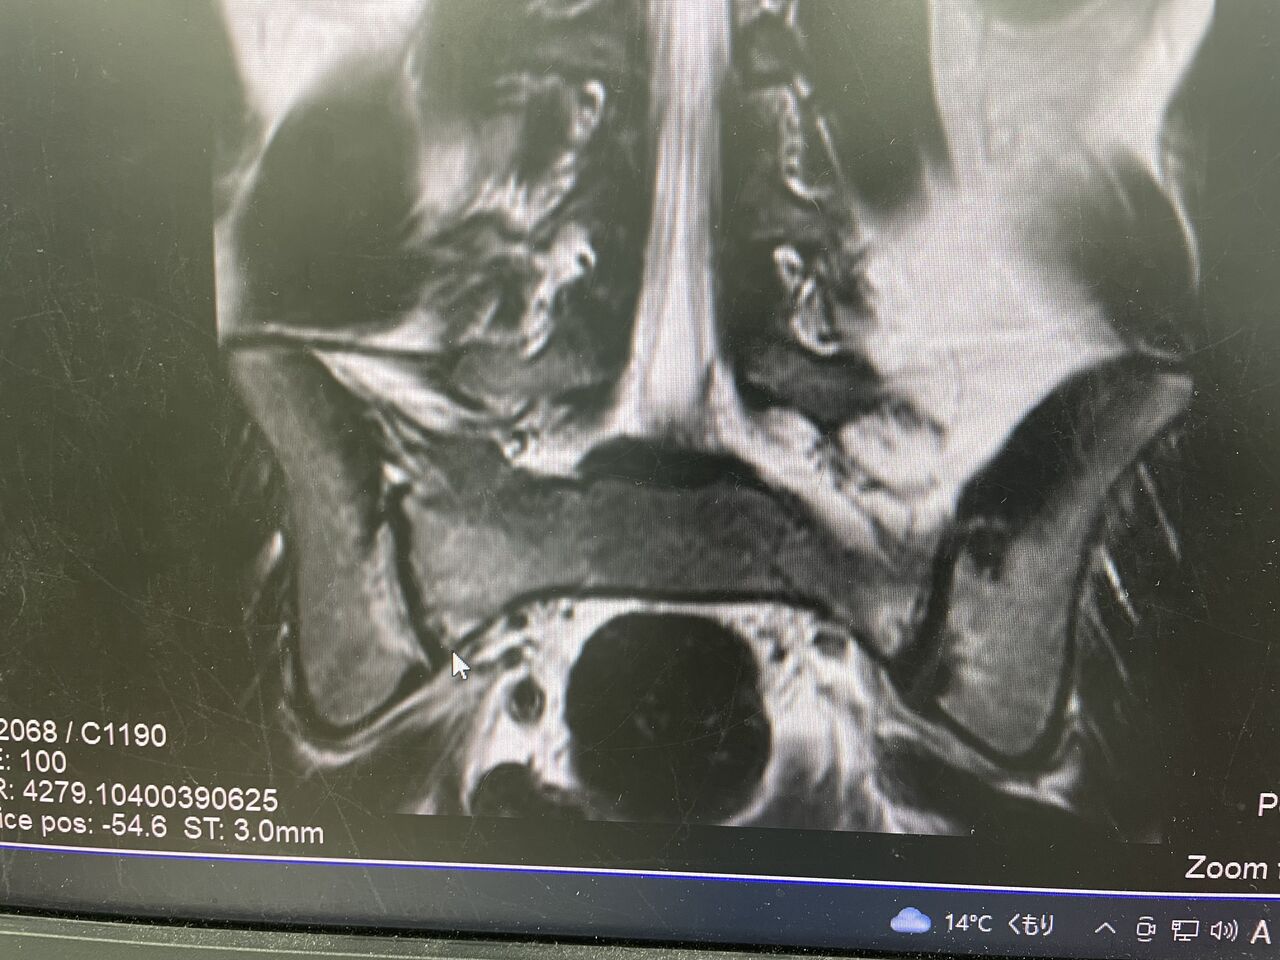

成長期は分離症が多いですよね

本日、勉強会の後、

午後の診療だけでも、3人の分離症の患者様が来られました

その中で、16歳での、分離サインがあり、

年齢的に、発症はないと考えておりましたが、

痛みが強すぎるため分離症を疑い、

MRIとCTを取りました、

時々ありますが、仙骨の疲労骨折と言うものもあります、

実際に分離症との鑑別は大事ですね

本日、早期復帰のため、

分離症の勉強会しました

3ヶ月で直すためには、

超早期の診断が必要ということがわかりました

早ければ3ヶ月で直した症例はたくさんあります

成長期で、進展時の痛みがあれば、

早めに病院来るのが大事ですね